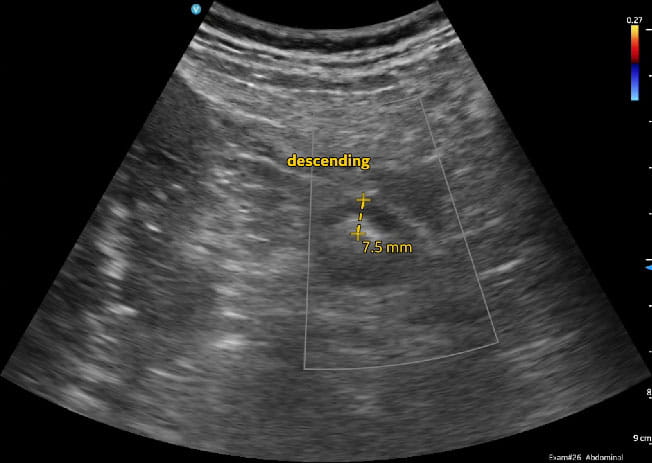

Intestinal Ultrasound of IBD Innovations in DH Fall 2024Caption: Wall thickening of the neo-terminal ileum in a patient with Crohn's ileitis.

Intestinal Ultrasound of IBD Innovations in DH Fall 2024Caption: Patient with active ulcerative colitis involving the left colon.